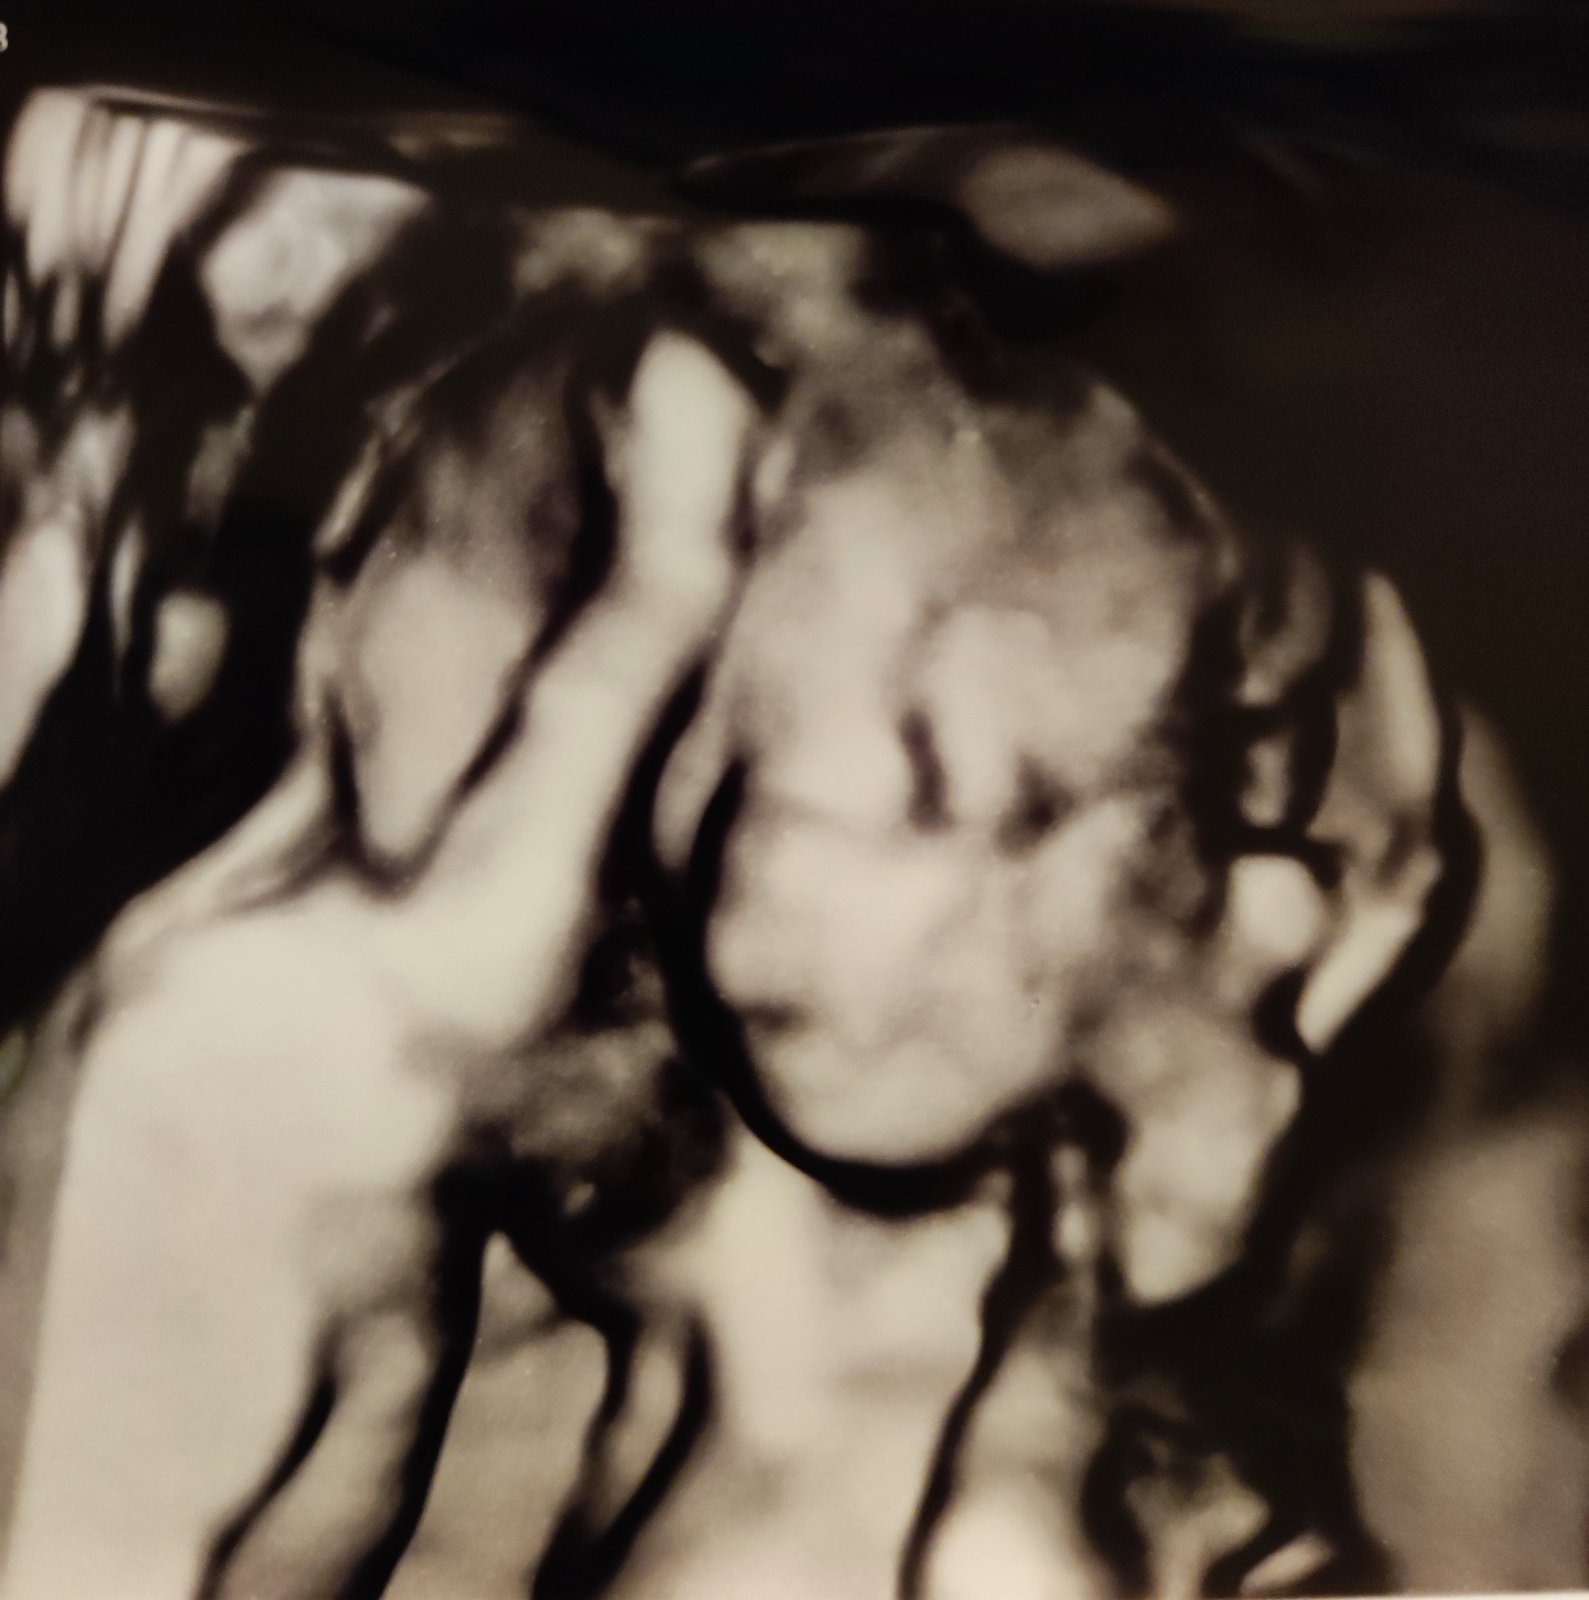

@adika_pl mojho muza jedineho vyber mena absolutne neberie, ten je spokojny, ze dal vsetkym priezvisko a viac sa neangazuje 😂 Mame este cas, ale aj tak to uteka, dnes mame sono v 17.tyzdni...

@anjelicek26 ako si dopadla na sone?

@adulka25 136g🥰🥰

@anjelicek26 som rada, že je všetko v poriadku a že drobček krásne rastie 🥰😍❤️

@adulka25 Uz zacinam byt kludnejsia,ze sa dockame zazraku🥰🥰